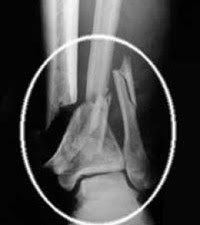

A bone fracture is the interruption of the continuity of the bone. It may be a crack in the bone, but also being completely broken in pieces of the bone.

Complexity of the fracture

A fracture may be single, in other words, there is only one break in the bone segment.

In the multiple faults under distinguish:

- bifocal fracture; these are two breaks in the same bone.

- the multifocal fractures; at least three fractions in the same bone.

- the comminuted fracture; shattering the bone with very many fragments.